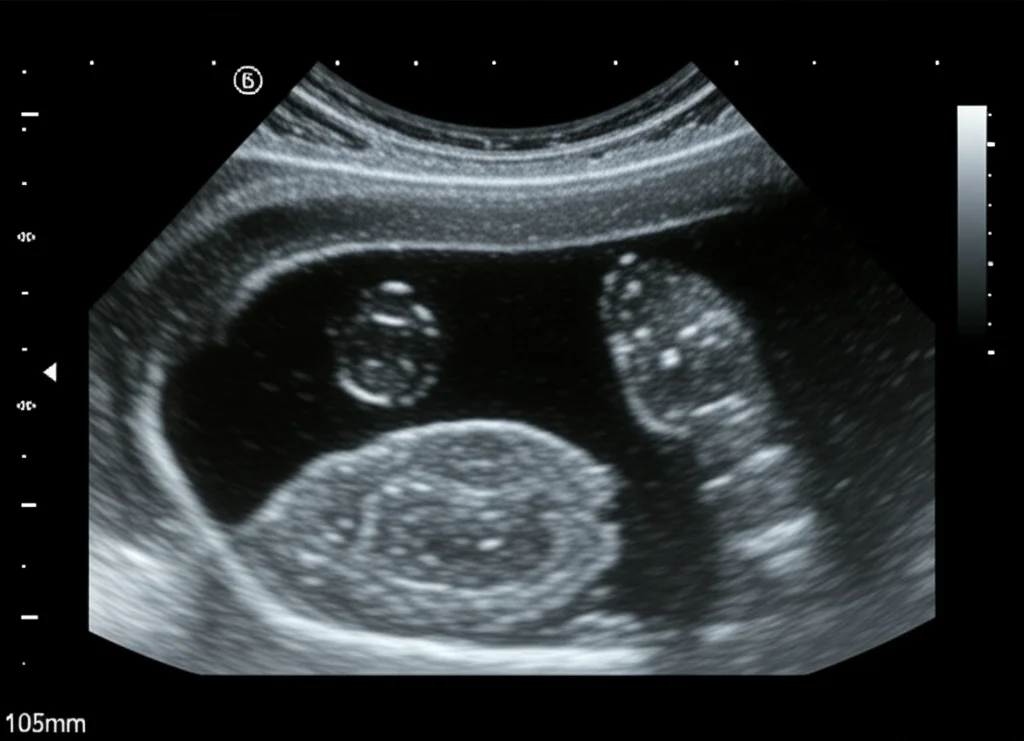

Traditionally, when you suspect PCOS, the doctor usually sends you for an ultrasound. It’s the go-to tool to peek at the ovaries, see their size, shape, and count those little cysts. It’s a vital step, no doubt.

But here’s the thing: looking at ultrasound images and counting those tiny follicles manually? *Phew*, it can be tough! It takes time, and honestly, what one doctor sees might slightly differ from what another sees. We call that inter-observer variability, and it can make diagnosis a bit less consistent than we’d like. For something as important as PCOS diagnosis, where prompt and accurate results are key to starting the right treatment and preventing potential complications, we really need something more precise and streamlined.

Ultrasound images, while useful, can sometimes lack detail. Think of them like slightly fuzzy photos. To get the best results, we need those images to be crystal clear. Our QEI-SAM model uses something called Enhanced Super Resolution Generative Adversarial Networks (ESRGAN) for this first step.

Once the image is looking sharp, the next crucial step is finding *exactly* where the cysts are. This is where the Segment Anything Model (SAM) comes into play. SAM is pretty revolutionary because it’s designed to segment… well, *anything*! We’ve adapted it specifically for ultrasound ovary images to segment the ovarian cysts.

SAM is like having an incredibly precise digital scalpel that can automatically draw a perfect outline around each cyst. This is vital for accurate diagnosis because things like the number and size of follicles are key criteria. Unlike many older segmentation models that need tons of specific training data for medical images, SAM is much more flexible. It can handle the variations and speckle noise often found in ultrasounds without needing extensive retraining. It just *works*. We evaluated how well SAM segmented the cysts using metrics like the Dice coefficient and IoU score, and it achieved the highest scores compared to other segmentation techniques: a Dice coefficient of 0.9501 and an IoU score of 0.9050. That’s seriously accurate outlining!